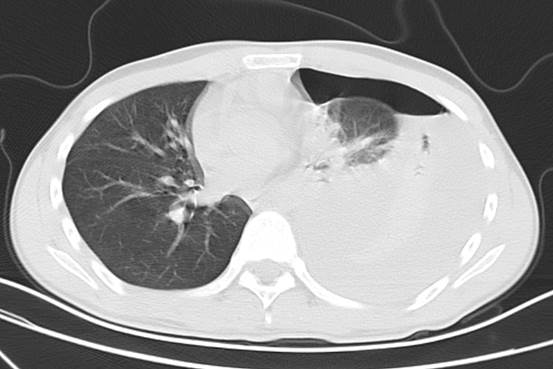

小陈的影像CT检查提示,左侧肺部压缩90%,相当于影像片上,左肺有九成大小“消失了”,他随即被收住入院。